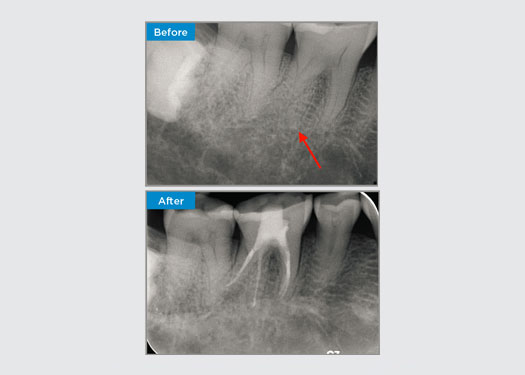

Der Patient stellte sich mit einer asymptomatischen apikalen Parodontitis an Zahn 34 vor. Auf dem präoperativen Röntgenbild war Zahn 34 mit zwei sichtbaren Wurzeln zu erkennen. Ein DVT-Scan bestätigte jedoch, dass es sich um einen dreifach verwurzelten Prämolaren handelte und dass sich die Kanäle in der Mitte der Wurzel in drei Kanäle aufteilten. Für diesen empfindlichen Zahn ist eine sorgfältige Feilenauswahl entscheidend.

In dieser Situation ist die Erhaltung der Zahn-/Wurzelstruktur von entscheidender Bedeutung, um das Risiko von Vorsprüngen, Verschiebungen, Abrissen, Perforationen und Wurzelfrakturen zu verringern. Fallauswahl, Diagnose und Behandlungsplanung sind wichtig. Die Auswahl von endodontischen Feilen, die flexibel und effizient sind und die natürliche Wurzelanatomie respektieren, ist entscheidend.